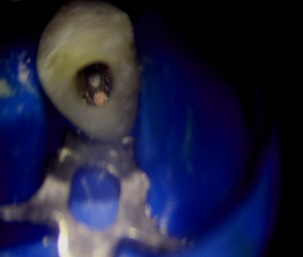

Perfurações dentarias são complicações no tratamento de canal que na maioria dos casos resulta em um prognóstico desfavorável, pois permite a entrada de microrganismos nos tecidos que envolvem o dente. Em alguns casos, devido ao seu difícil diagnóstico, acesso limitado, tempo decorrido ou tamanho da perfuração resultará em um desafio para o profissional conseguir um selamento adequado da área, sendo muito importante o conhecimento sobre o material que será empregado.